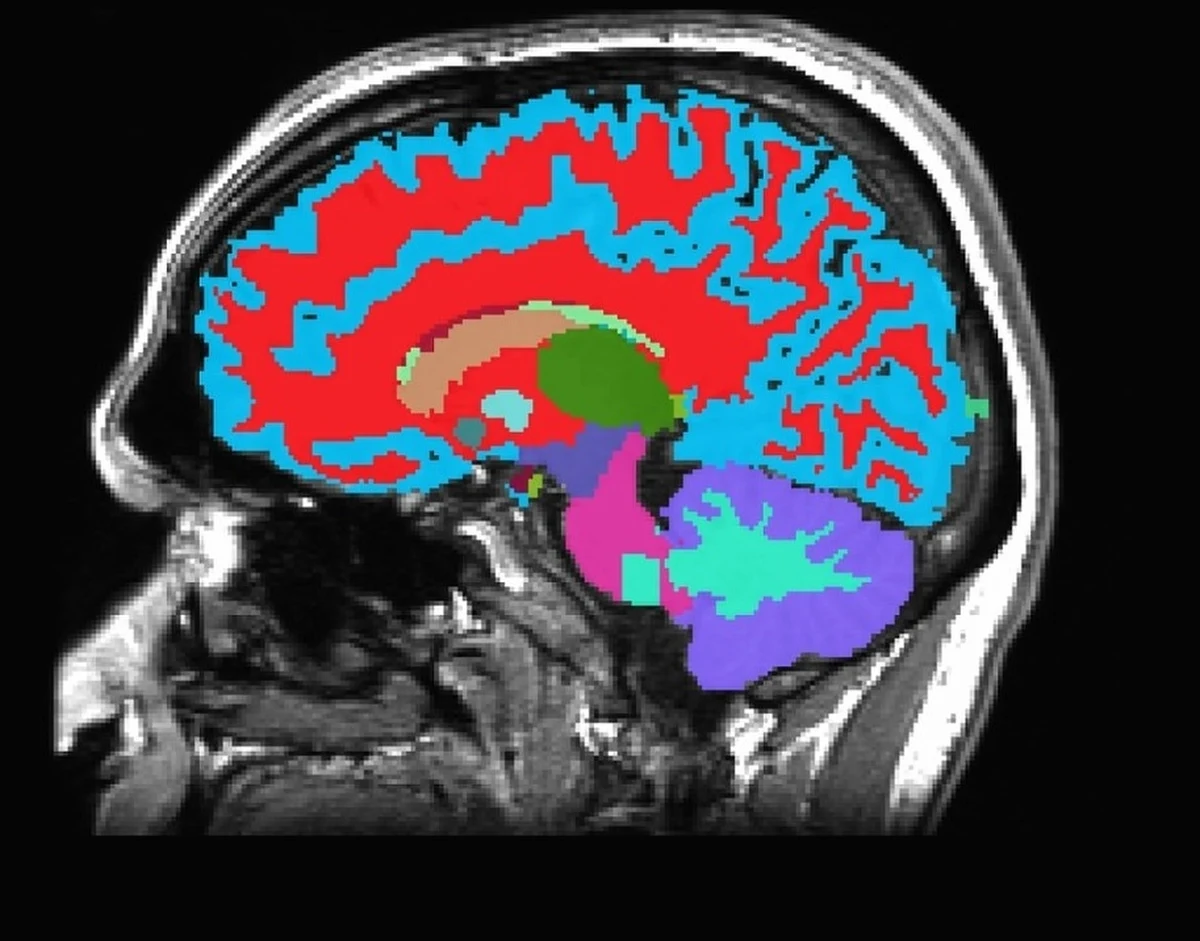

Czy można z pomocą nowoczesnych, nieinwazyjnych metod diagnostycznych ocenić, jak szybko się starzejemy i przewidzieć, jakie choroby mogą nas czekać za kilka, a nawet kilkanaście lat? Naukowcy ze Stanów Zjednoczonych i Nowej Zelandii pokazują, że odpowiednia analiza obrazu rezonansowego mózgu może to umożliwić. Przekonują, że opracowane przez nich narzędzie DunedinPACNI, pozwala na oszacowanie tempa starzenia mózgu i ryzyka rozwoju chorób takich jak demencja, zanim pojawią się pierwsze objawy.

DunedinPACNI na podstawie pojedynczego badania MRI mózgu potrafi już w wieku średnim wskazać, kto jest bardziej narażony na rozwój przewlekłych chorób, które zwykle pojawiają się dopiero po wielu latach. Taka wiedza może być impulsem do zmiany stylu życia i diety, zanim pojawią się pierwsze symptomy choroby. W przypadku osób starszych narzędzie pozwala przewidzieć, czy w przyszłości rozwiną się u nich objawy demencji lub innych schorzeń związanych z wiekiem - także na długo przed ich wystąpieniem.

Następnie naukowcy z pomocę technik uczenia maszynowego wytrenowali algorytm, by na podstawie jednego skanu MRI mózgu - wykonanego w wieku 45 lat - potrafił przewidzieć ten wskaźnik. Narzędzie przetestowano także na innych grupach z Wielkiej Brytanii, USA, Kanady i Ameryki Łacińskiej.